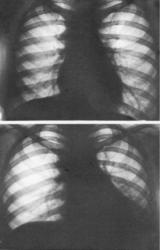

2 степень сужения бронха - клапанная эмфизема (иллюстрация 6) обуславливает следующую теневую картину:

- увеличение прозрачности легочного фона структурной единицы лёгкого (доли, сегмента);

- увеличение объёма структурной единицы лёгкого;

- обеднение сосудистого рисунка сегмента структурной единицы – иллюстрация 7 (Заимствована из монографии «Рентгенодиагностика заболеваний органов дыхания». Авторы: Л.С. Розенштраух, Н.И. Рыбакова, М.Г. Виннер. М., «Медицина», 1987). Верхний снимок произведен на вдохе, нижних – на выдохе.

На этом этапе при рентгенотелевидении может фиксироваться симптом Гольцкнехта – Якобсона. Необходимо подчеркнуть, что на данном этапе наиболее информативны рентгенограммы, произведенные на «максимальном вдохе».